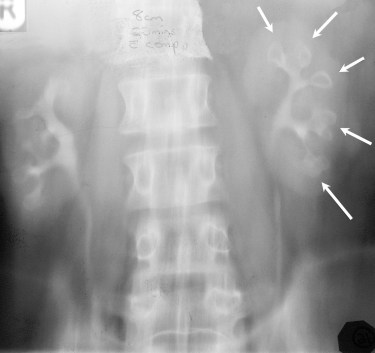

Signo de necrosis papilar en la urografía. La papila desprendida se ve como una defecto de repleción radiotransparente que ocupa la totalidad de su cáliz salvo un fino contorno radioopaco (flechas).

Esquema que muestra diferentes patrones de excavación de la necrosis papilar. A) normal. B) Excavación central cuyo aspecto se ha descrito como Signo de la pelota de golf en el tee (el tee es la pieza cuya forma es parecida a un clavo y en la que se apoya la pelota de golf para golpearla). C) Excavación del fórnix. D) Excavación con aspecto de pinzas de cangrejo o de langosta. E) Signo del anillo a anillo de sello. F) Papila desprendida con cáliz abombado.